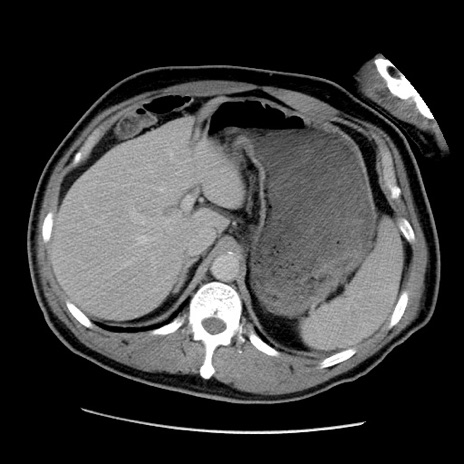

症例22(横断像)

【症例】50歳代男性

【主訴】腹痛

【現病歴】AVMからの被殻出血のため回復期リハ病棟入院中。 本日午後3時頃急に下腹部痛が出現した。

【既往歴】AVM、被殻出血、虫垂炎、高血圧

【身体所見】意識晴明、左半身不全麻痺、会話の理解は良好、36.5°C、腹部:膨隆、全体に板状硬、下腹部正中に圧痛点あり、反跳痛-、筋性防御不明、右下腹部にope scar

【データ】WBC 9400、CRP 0.06